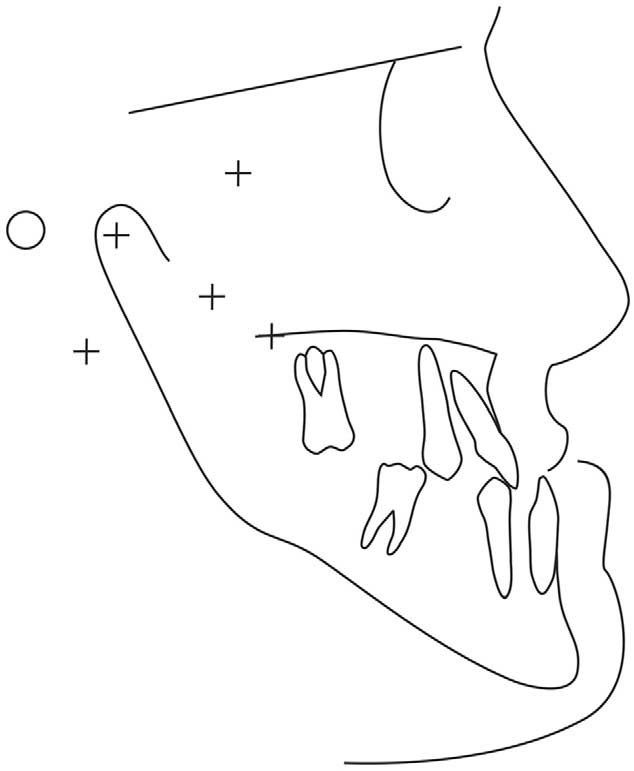

A 27-year-old woman came to the private office of the second author for orthodontic treatment. Her major reason for seeking treatment was to improve her facial esthetics. Clinical examination showed a typical skeletal Class III facial pattern, with severe mandibular prognathism, retruded upper lip, procumbent lower lip, and increased lower anterior face height. Her intraoral examination showed Class III molar and canine relationships with anterior and transverse bilateral crossbites (Fig 1). Slight irregularity of the maxillary and mandibular teeth was evident, and the curve of Spee was mild (Fig 2). The panoramic radiograph showed the absence of the right maxillary second premolar and the mandibular first molar, and the left maxillary and

mandibular first molars (Fig 3). Cephalometrically, the patient had a short posterior face height characterized by a short ramus and high gonial and mandibular plane angles, and a proportionally increased lower anterior face height.3 The maxillary central incisor was in good relationship with the basal bone, but the mandibular central was lingually tipped, compensating for the A-P discrepancy (Fig 4, Table). There was sound periodontal support, indicating that conventional orthodontic therapy could be undertaken.

Fig 4. Pretreatment cephalometric tracing.